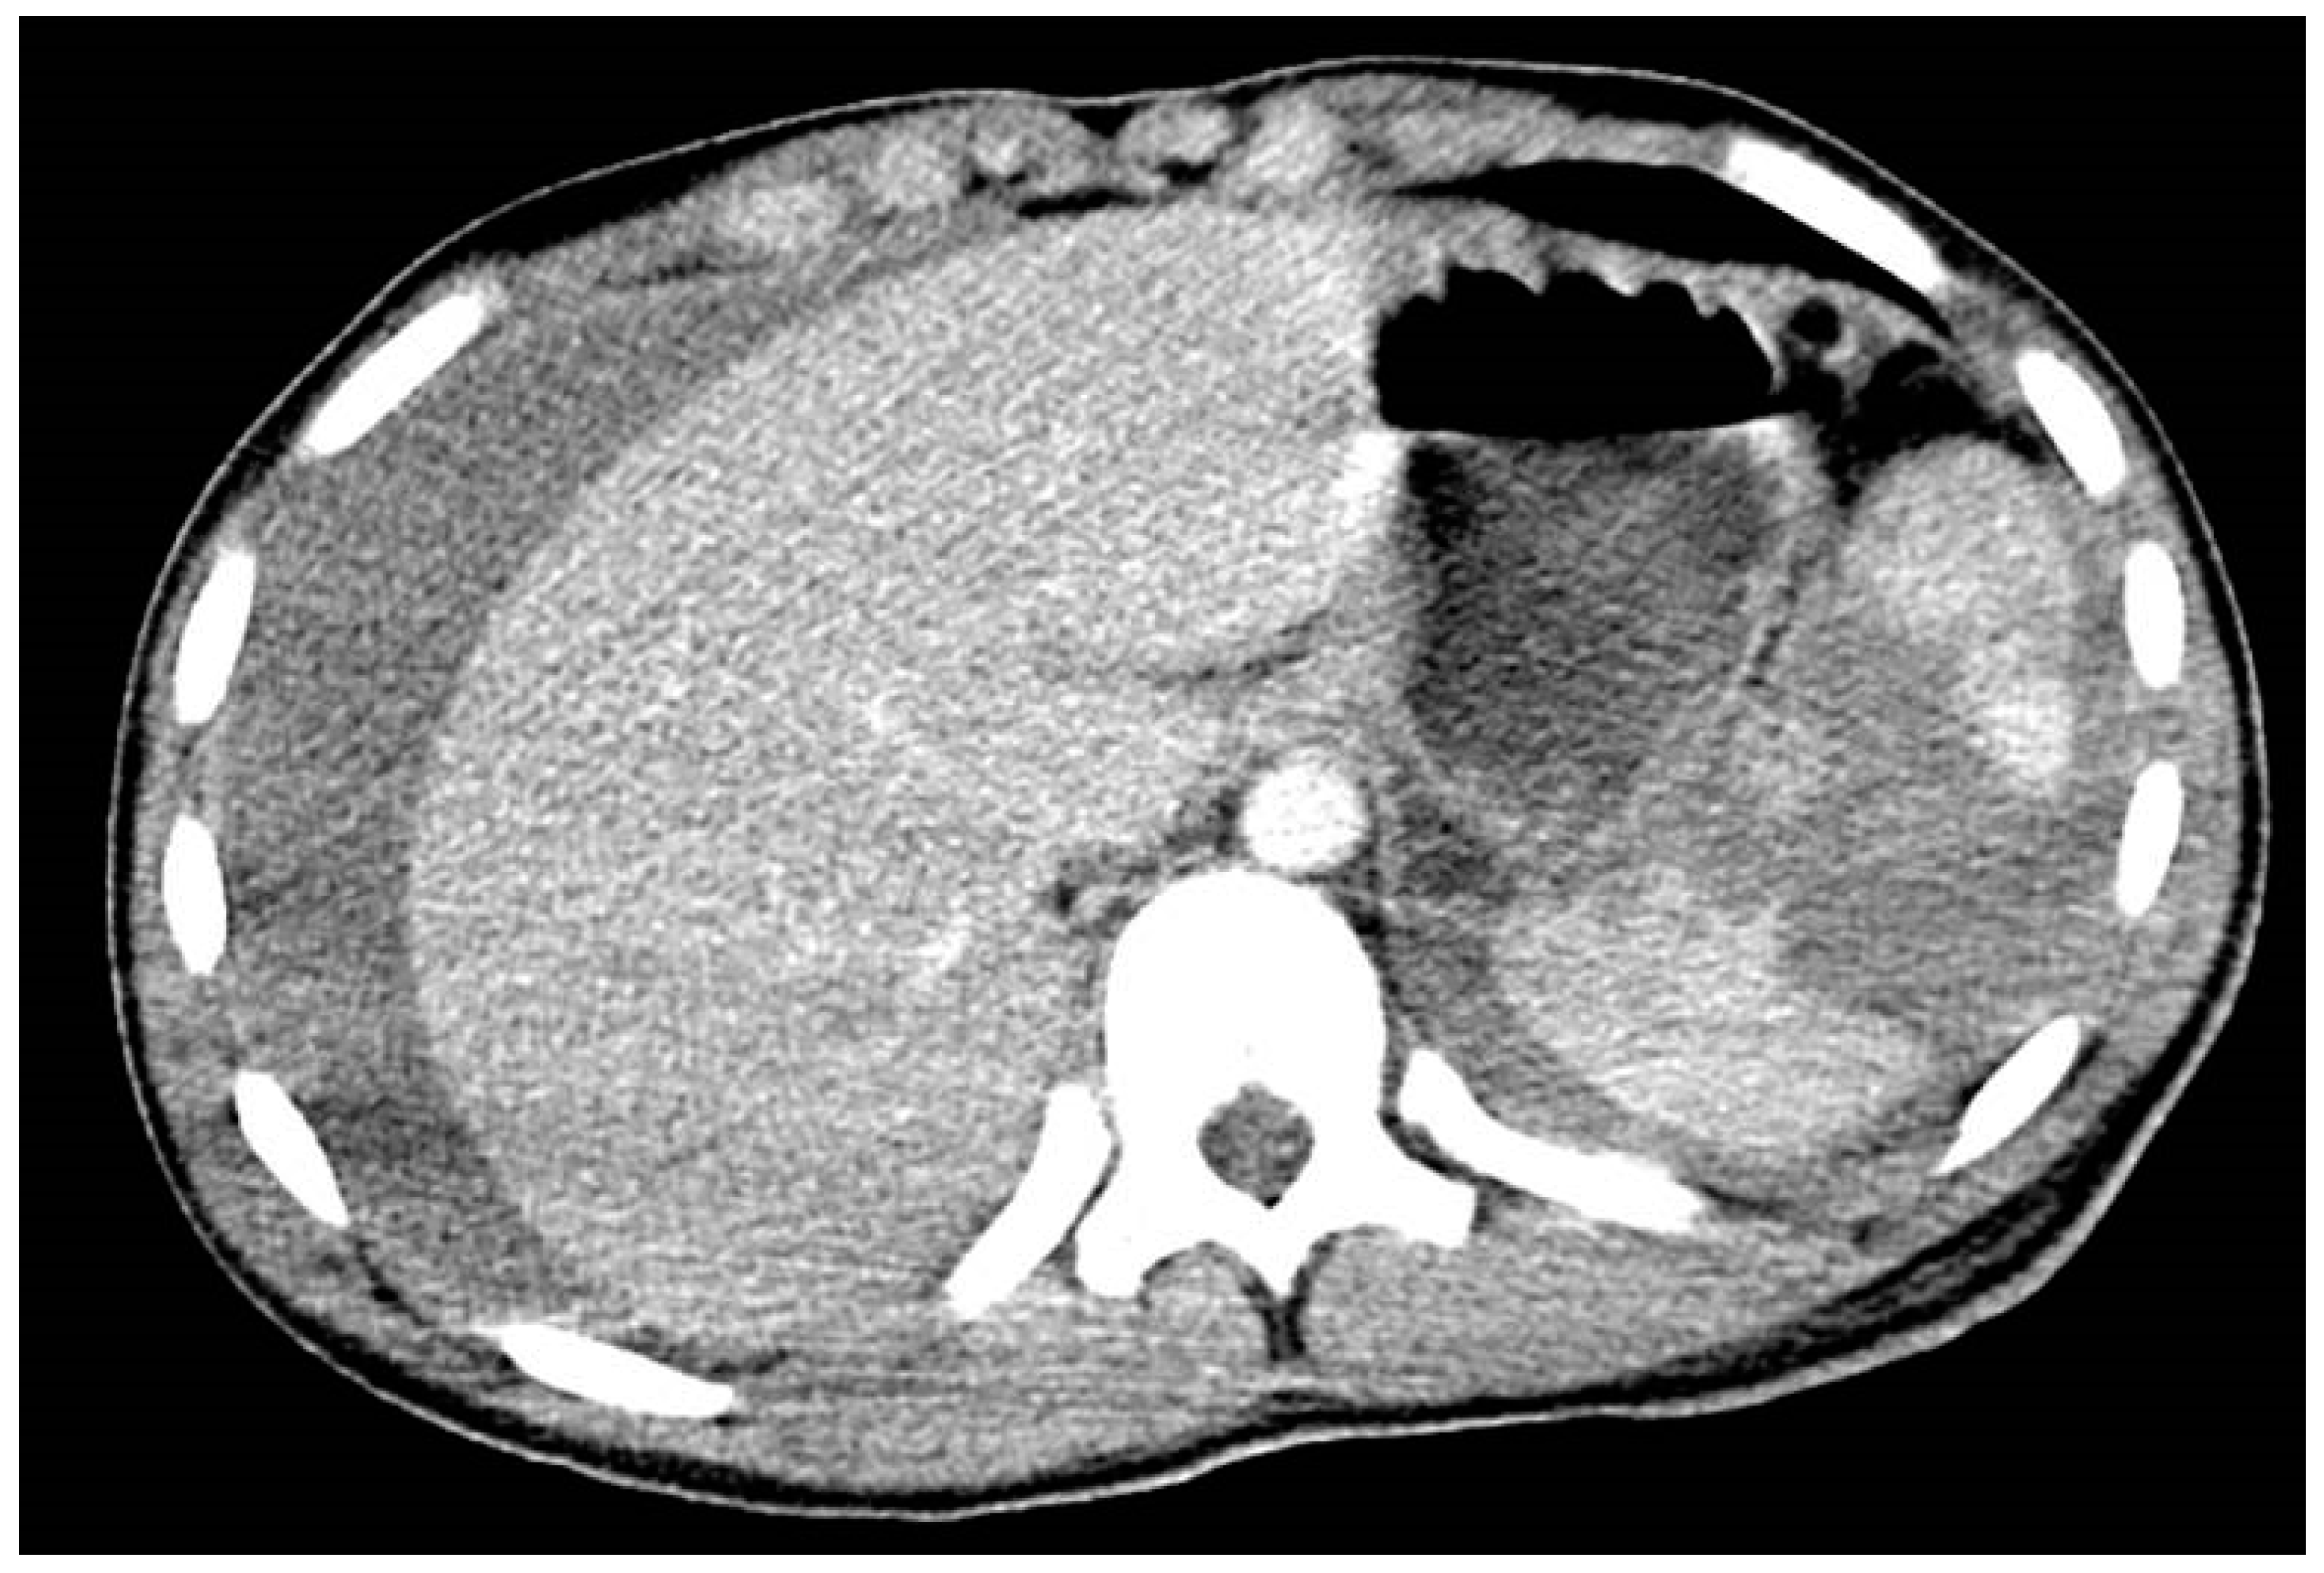

8.1. Kidney Injury

- Brown, S.L.; Elder, J.S.; Spirnak, J.P. Are pediatric patients more susceptible to major renal injury from blunt trauma? A comparative study. J. Urol. 1998, 160, 138–140. [Google Scholar] [CrossRef]

- Brown, S.L.; Haas, C.; Dinchman, K.H.; Elder, J.S.; Spirnak, J.P. Radiologic evaluation of pediatric blunt renal trauma in patients with microscopic hematuria. World J. Surg. 2001, 25, 1557–1560. [Google Scholar] [CrossRef] [PubMed]

- Hagedorn, J.C.; Fox, N.; Ellison, J.S.; Russell, R.; Witt, C.E.; Zeller, K.; Ferrada, P.; Draus, J.M., Jr. Pediatric blunt renal trauma practice management guidelines: Collaboration between the Eastern Association for the Surgery of Trauma and the Pediatric Trauma Society. J. Trauma Acute Care Surg. 2019, 86, 916–925. [Google Scholar] [CrossRef]

- Eassa, W.; El-Ghar, M.A.; Jednak, R.; El-Sherbiny, M. Nonoperative management of grade 5 renal injury in children: Does it have a place? Eur. Urol. 2010, 57, 154–161. [Google Scholar] [CrossRef]